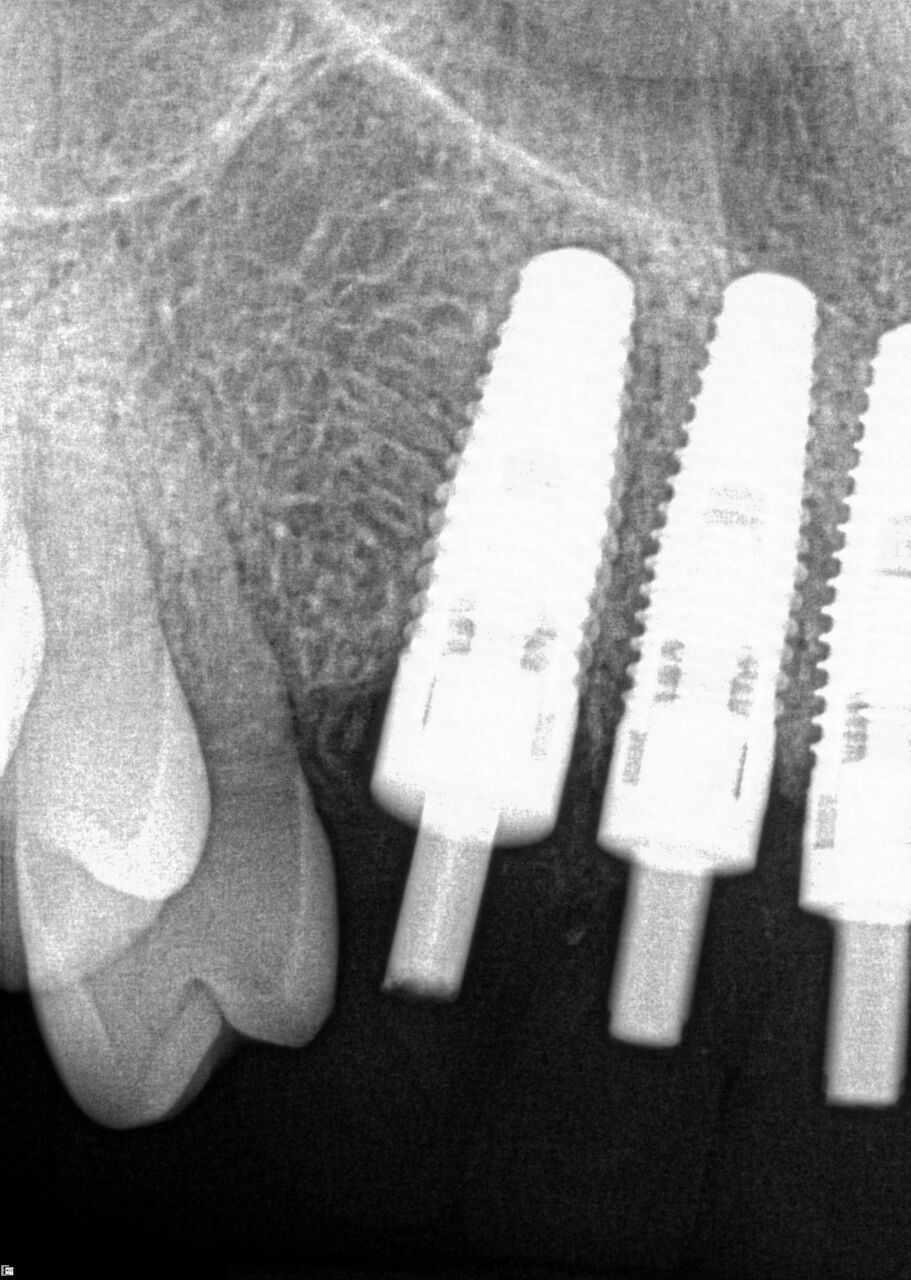

(24.) Radiograph of postoperative individual crowns on Nos. 6 through 10.

Figure 24

(25.) Radiograph of postoperative individual crowns on Nos. 6 through 10.

Figure 25

A 42-year-old man presented with a very loose bridge on Nos. 6 through 9 with periodontally compromised retainers on Nos. 6 and 9 (Figure 17 through Figure 19), and endodontically involved No. 10 with a calcified canal. Teeth Nos. 6, 9, and 10 were extracted, the sockets fully debrided, and pontic soft tissue on Nos. 7 and 8 sculpted to be symmetrical in soft tissue contour with the contralateral lateral incisor and central incisor locations. Implants were secured in position Nos. 6 through 10 (Figure 20) in excess of 45 Ncm, the bone was milled to provide unimpeded seating of temporary abutments, and temporary crowns were fabricated chairside and adjusted to be out of occlusion in centric relation and all excursions. The temporary crowns were cemented after extrusion of excess cement extraorally and the patient was prescribed antibiotics, analgesics, and instructed in postoperative care particular to immediately provisionally restored implants. At 6 months, integration was confirmed (Figure 20 through Figure 23) and after placement of scanning abutments, the implants and soft tissues were scanned. Final crowns were fabricated from the scanned images and were cemented after extrusion of excess cement extraorally (Figure 24 through Figure 26), and oral hygiene procedures were reviewed.